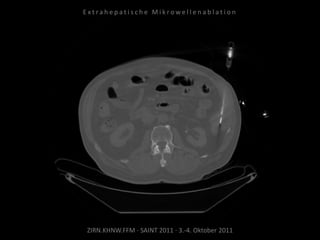

Bildgebung vor MWA:

CT 14.03.2011

Situation:

Nur 1 Metastase, diese ist jedoch

progredient. Kritische Lage in

Herznähe.